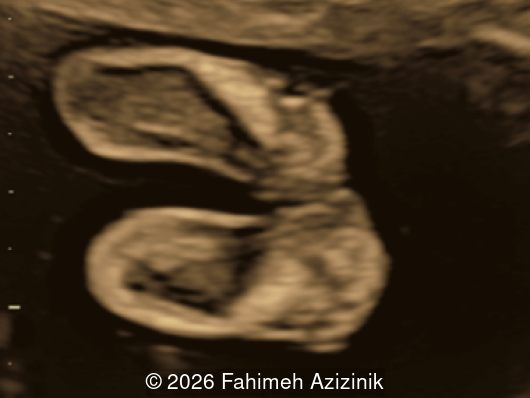

Image 2

• Complex syndactyly of the hands and feet. Complex hand brachysyndactyly with “mitten-like” appearance due to bony fusion of the fingers

Bicoronal synostosis is the characteristic cranial hallmark of Apert syndrome, detectable sonographically from 18 weeks. Its most recognizable manifestation is turribrachycephaly, defined by an elevated cephalic index (typically >85–90%) and a tall cranial vault with marked frontal bossing [19]. On prenatal ultrasound, the face in Apert syndrome shows midface hypoplasia with a depressed nasal bridge, proptosis, hypertelorism, and frontal bossing. The extremities demonstrate syndactyly of both bone and soft tissue of the hands and feet with partial-to-complete fusion often involving second, third, and fourth digits, known as “mitten hands” and “socked feet”. In severe cases, all digits are fused, with the presence of a single nail known as “synonychia” [20]. Other ultrasound findings include mild ventriculomegaly, agenesis of the corpus callosum, deficient or absent septum pellucidum, and fusion of the cervical vertebrae at the level of C5-C6 [21]. Cardiovascular (atrial and ventricular septal defect) and genitourinary anomalies (hydronephrosis, and cryptorchidia) are present in 10% of patients [22]. Increased nuchal translucency in the first trimester [23], widely open metopic suture [24], and polyhydramnios [25] have also been reported. Three-dimensional (3D) ultrasound facilitates assessment of surface abnormalities of the face and extremities, and magnetic resonance imaging (MRI) can be used to evaluate associated intracranial conditions [26].